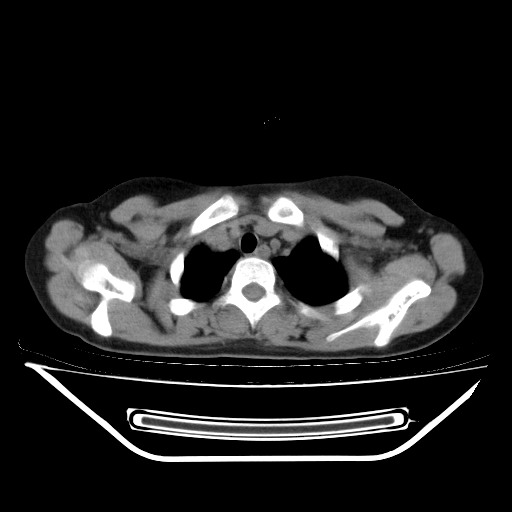

女,12岁,前期发热,咳嗽,无痰,经头孢抗炎无效。ct右肺上叶实变影.5天后公布病理结果。以下是2010-2-13ct片

经过胸部穿刺活检为支原体感染。以下示抗支原体感染30天后所见,病灶明显缩小,临床症状消失: